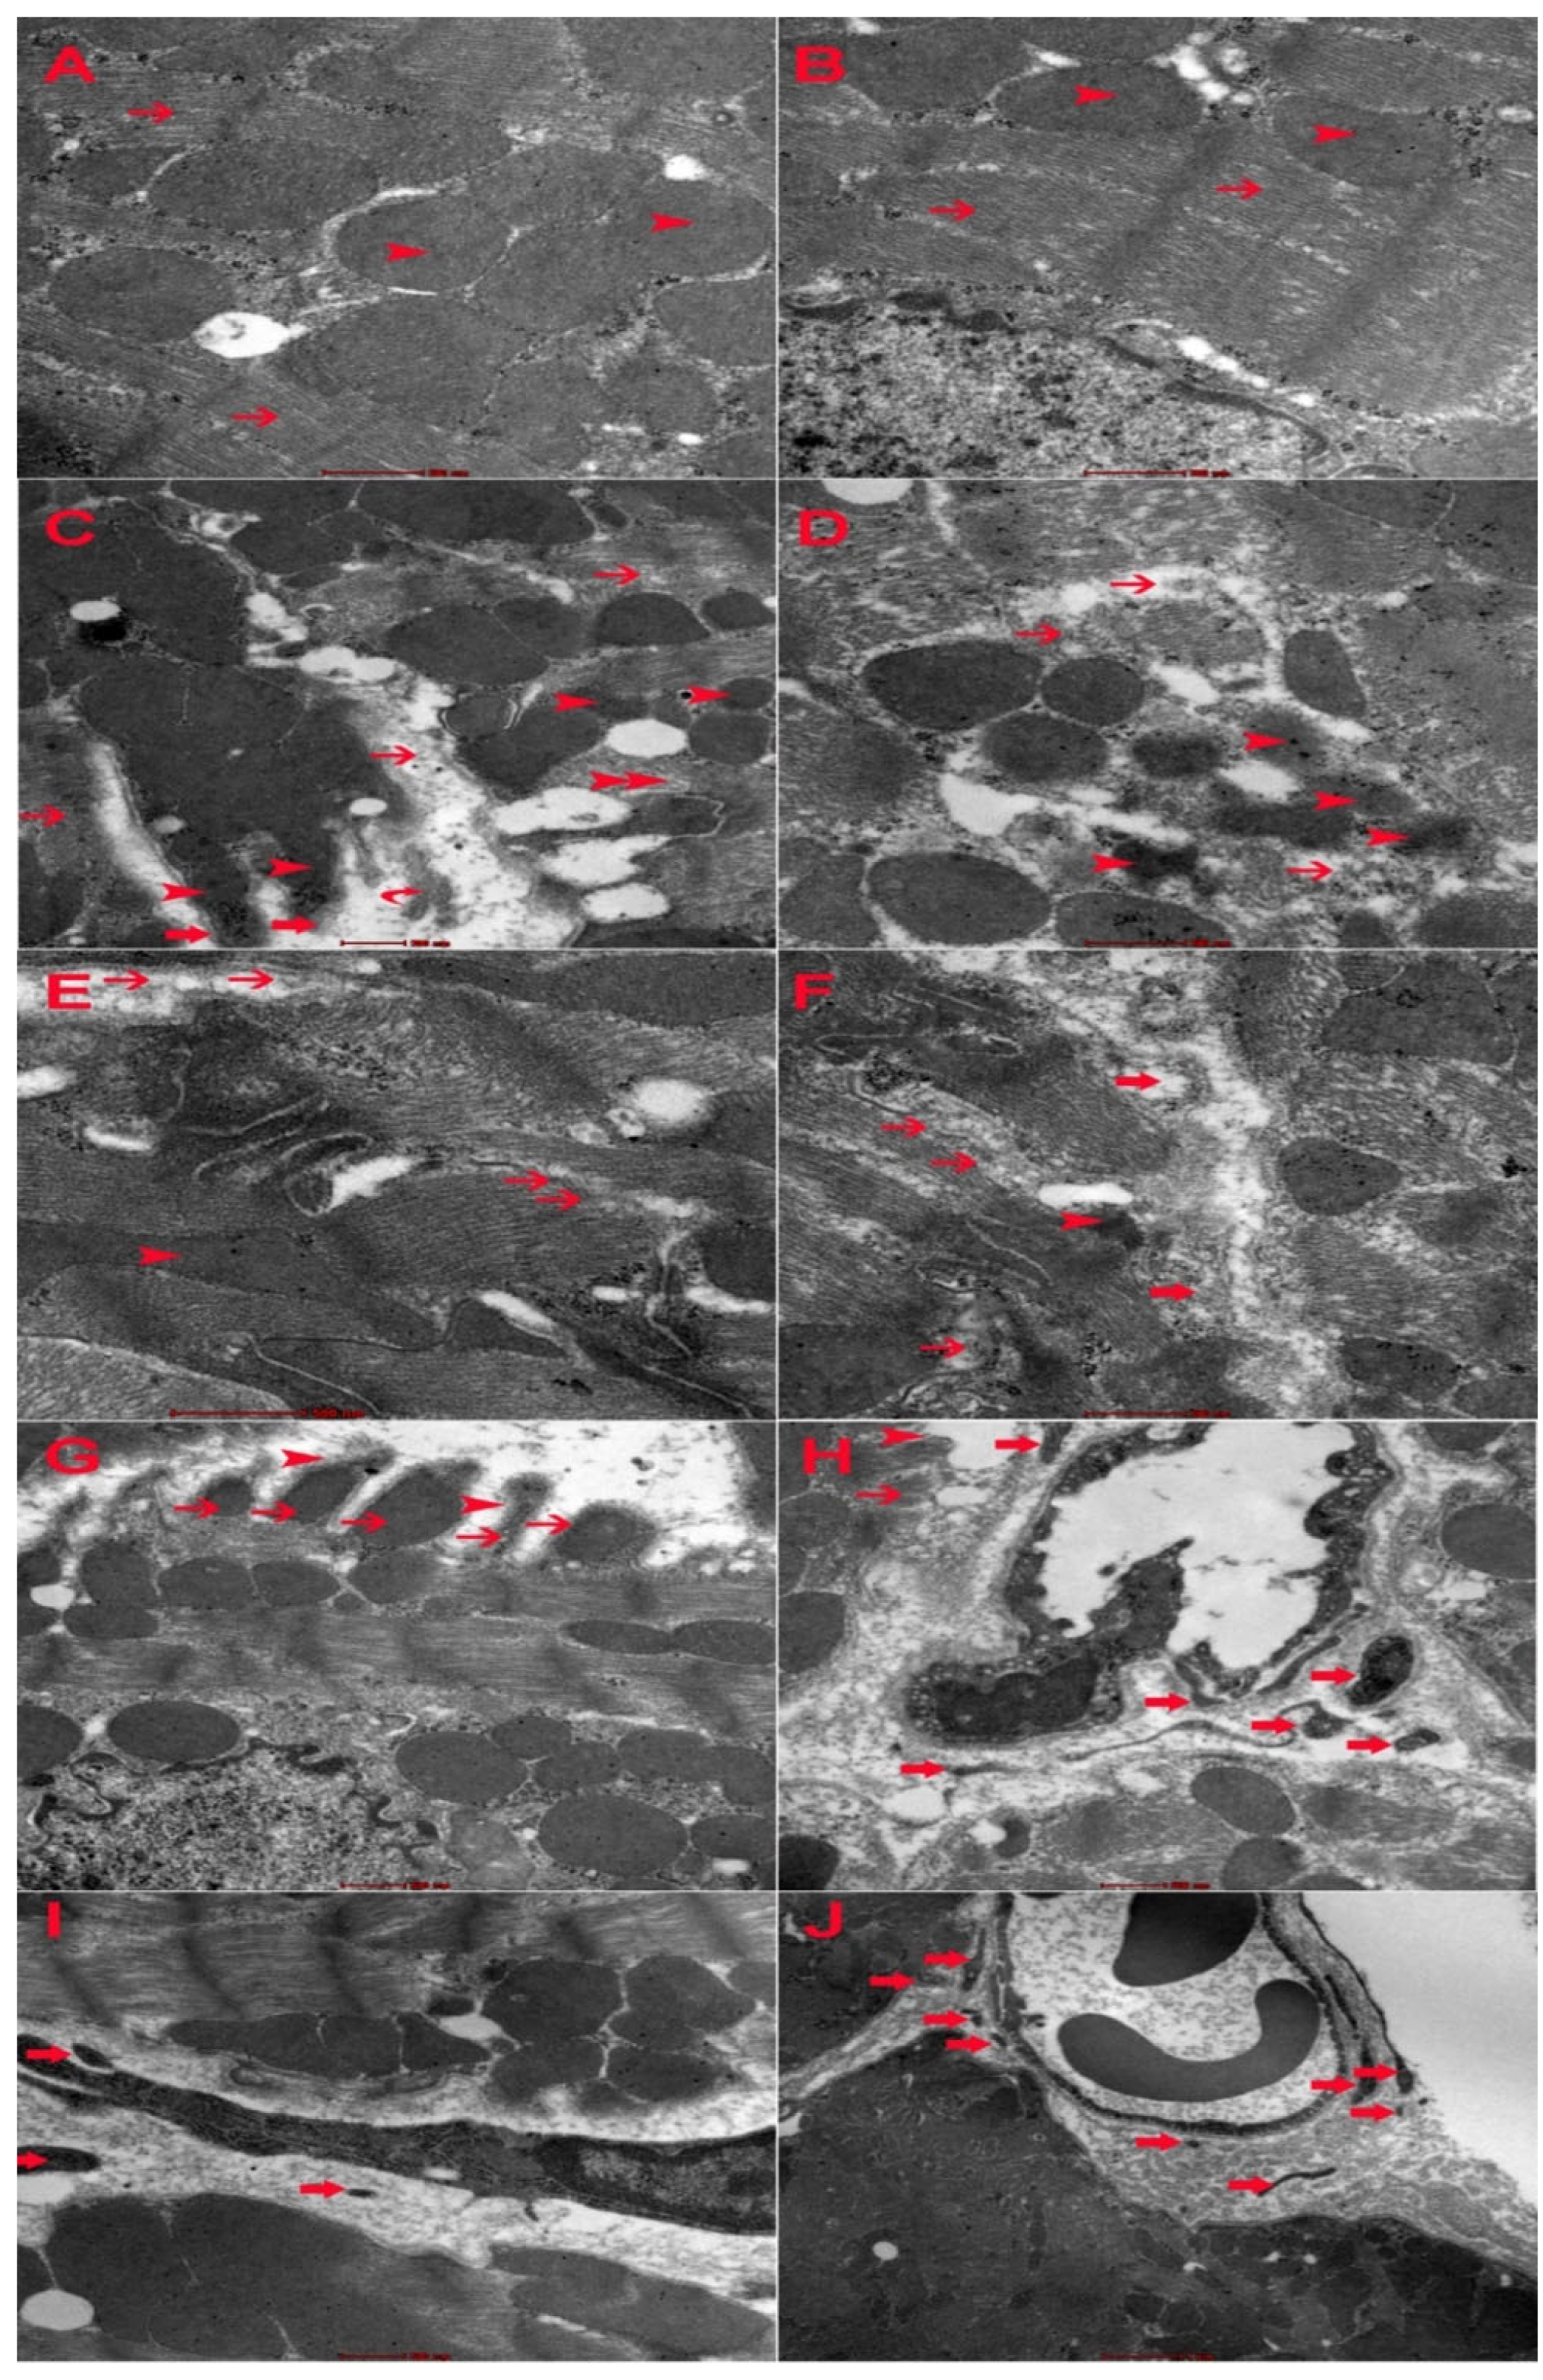

2.7. Electron Microscopic Changes